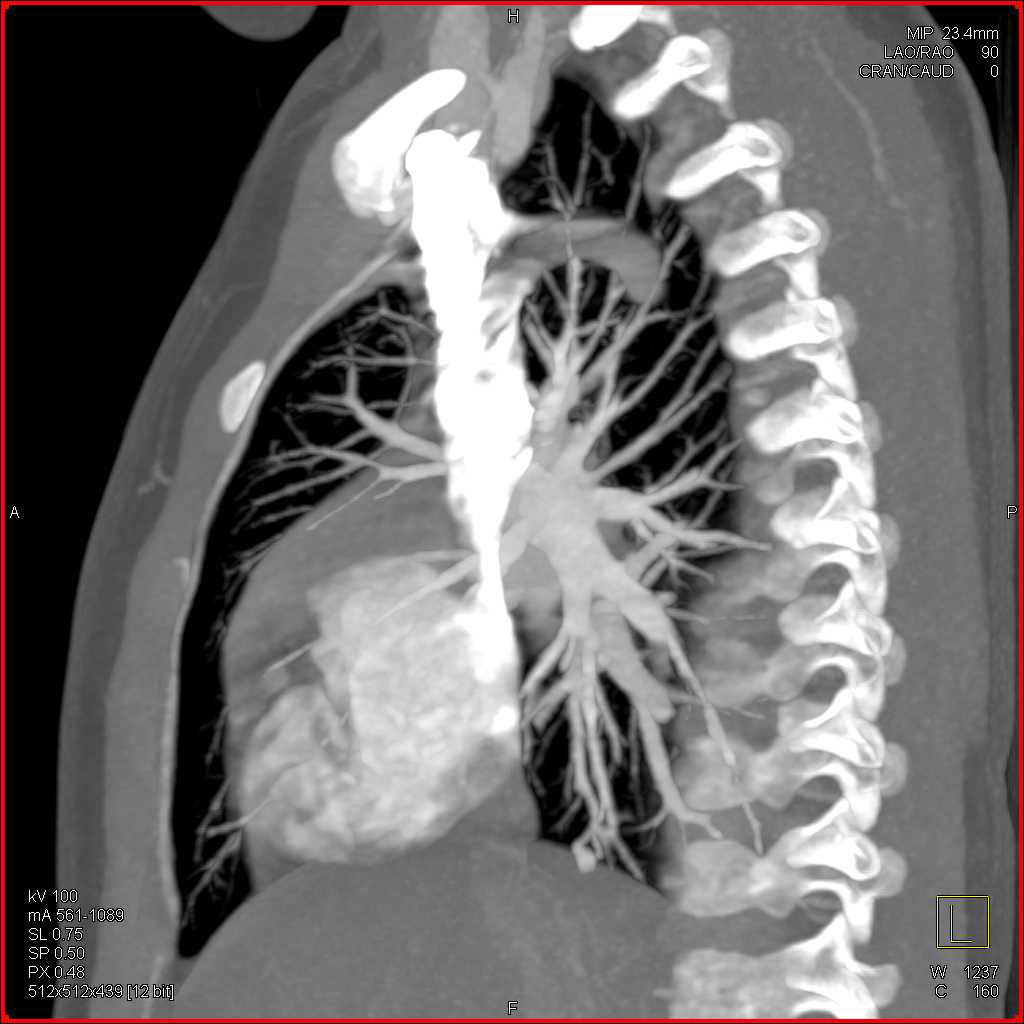

Metastatic Renal Cell cCarcinoma to the Lungs, Liver and Adenopathy